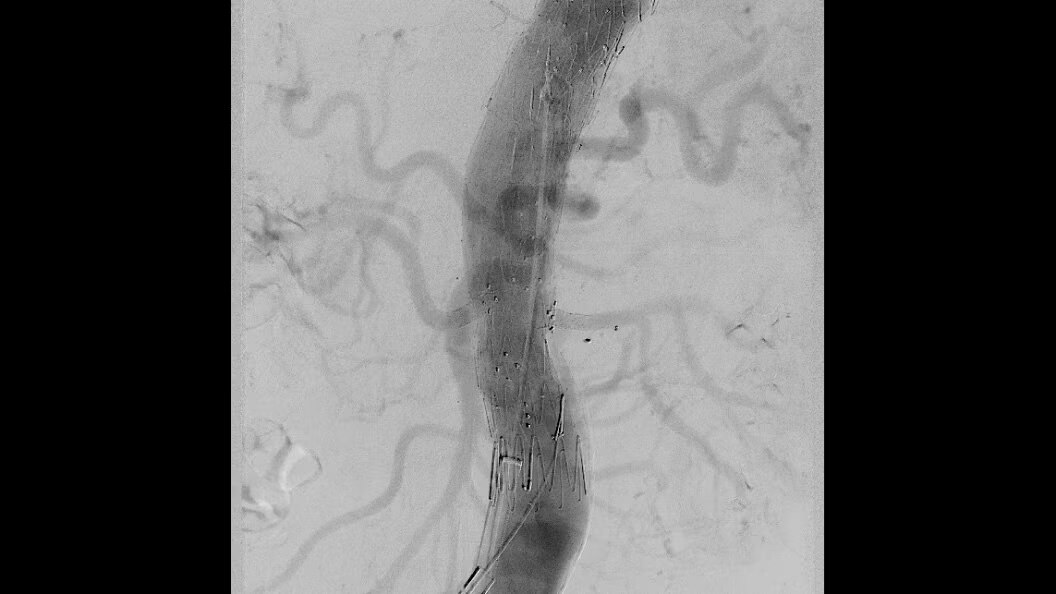

Liver ASSIST Virtual Parenchyma

Liver ASSIST Virtual Parenchyma, powered by Edison, is a 3D Visualization software solution designed to provide AI based virtual parenchymography to help you simulate injections dynamically and thus, perform liver embolization procedures with confidence.